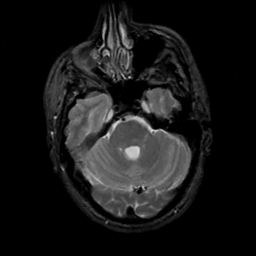

MR Study #5, March 10, 1991 -- Slice #15

[Home][Help][Clinical][Tour 1][Tour 2] Slice 15